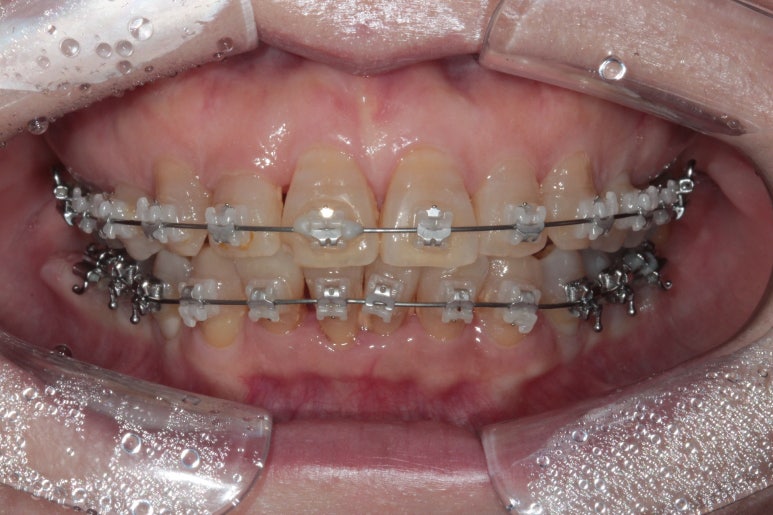

클리피씨 교정을 합니다.

TOMY 사의 클리피씨는 가장 많이 쓰이는 교정장치입니다.

위에 보이는 사진은 교정장치를 붙이고 불과 4개월 후 입니다!

생각보다 위턱 앞니가 빨리 가지런해 진 것을 확인할 수 있습니다.

아래 앞니만 조금 더 가지런해지면... 될 것 같은 느낌이네요.